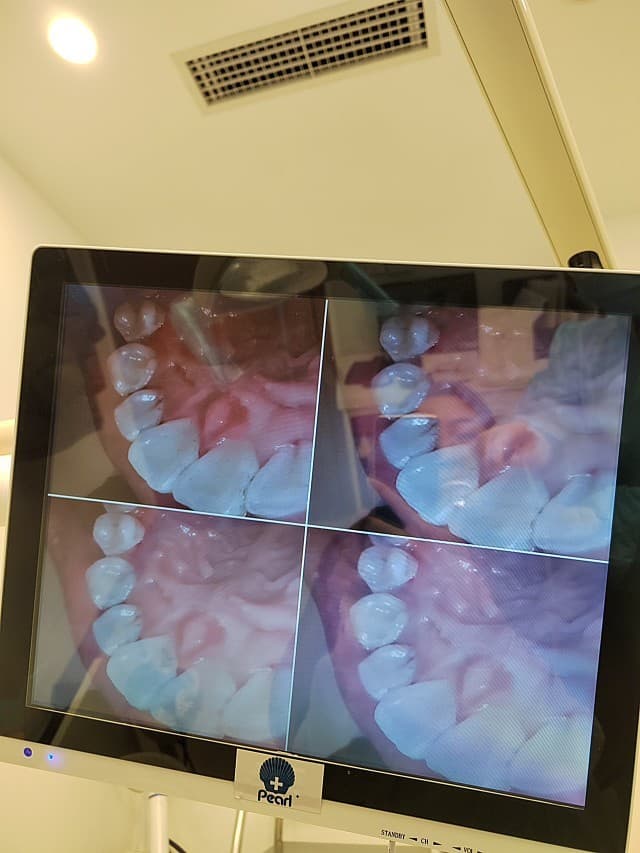

第一步: 医生会用类似点读笔的小仪器在口腔里照一圈,365度无死角牙渍全景高清大照就投在患者正前方,我那叫一个惊呆呆😳